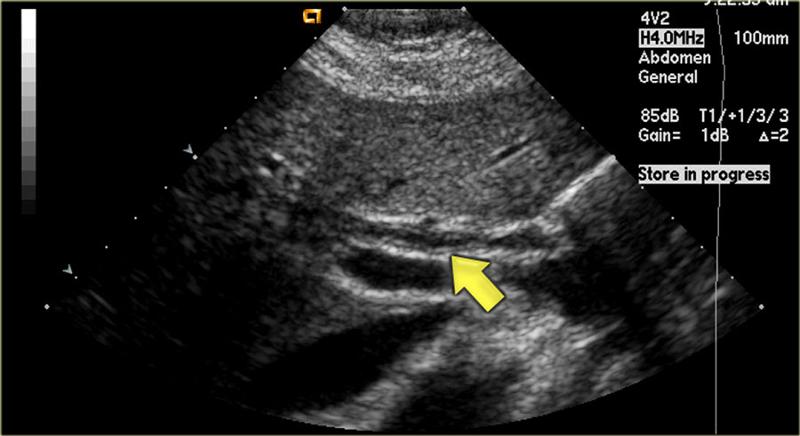

Диагностируется эта патология либо при помощи ультразвукового исследования (УЗИ), либо методом чреспеченочной холангиографии, которые позволяют определить не только наличие в протоках конкрементов, но также выяснить их локализацию, количество и размеры.

- УЗИ органов брюшной полости дает возможность выявить наличие и количество конкрементов в холедохе, а также отклонение от нормы ширины просвета протока и структурные нарушения печеночных тканей;